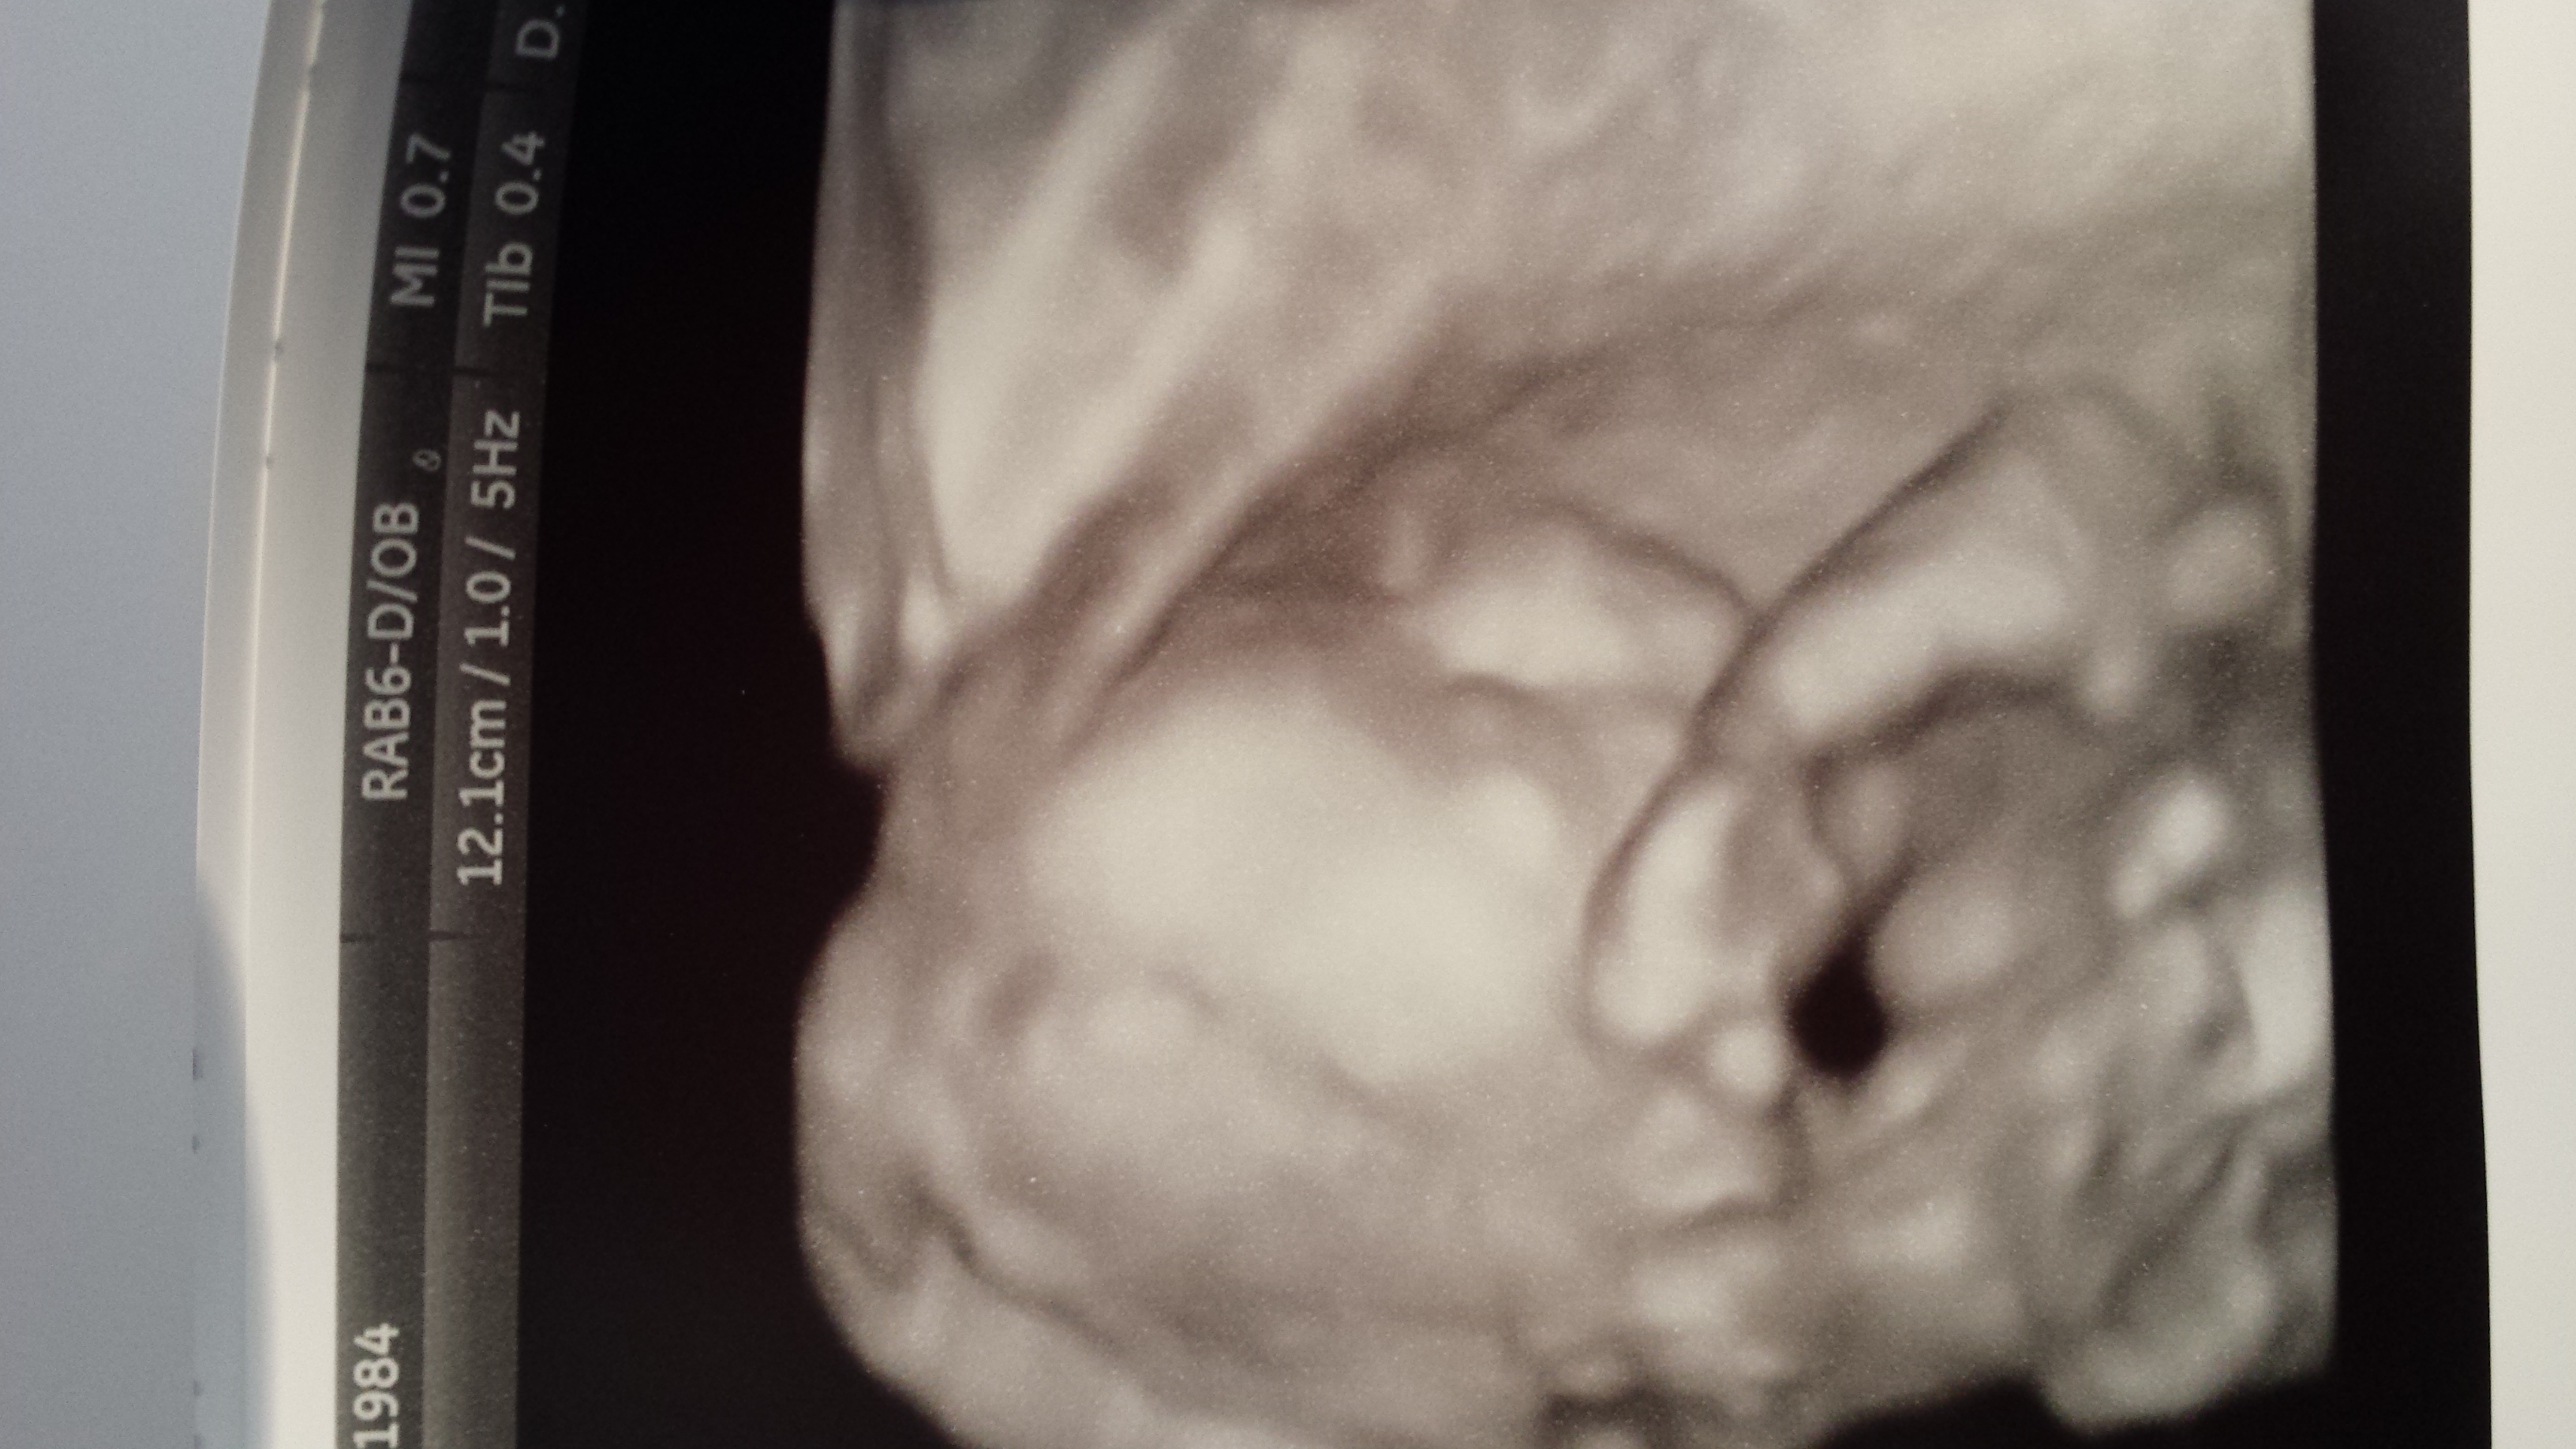

I used to think 3D ultrasounds were strange, especially since I never had one done during my first pregnancy. I went in today for a recheck on my A/S since baby wasn't cooperative the first time around and the tech switched between regular and 3D a couple of times. It was really neat to see the details and I think our picture came out somewhat looking like a baby at 21w3d (but maybe I'm biased). ;)

• @lilqt3929, I have to guess.. is it almost a top view and baby has his/her hand by the side of his/her face?

@lilqt3929, I have to guess.. is it almost a top view and baby has his/her hand by the side of his/her face?

Yes you're right, he was trying to hide his face from us. I'm the same way looking at these pictures, need the comfirmation to know what I'm looking at even with the regular pictures.